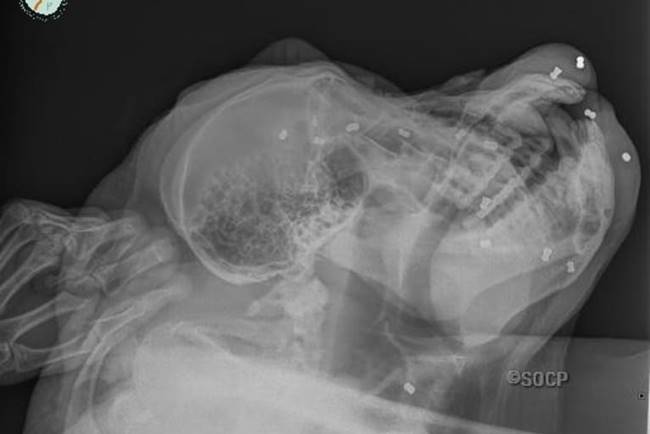

ลิงอุรังอุตังถูกพรานยิงปืนอัดลมใส่ กระสุนฝังทั่วร่าง เจาะทะลุกะโหลก 16 นัด สัตวแพทย์เร่งช่วยเหลือ เผยโดนยิงจนตาบอด ผ่ากระสุนออกหมดไม่ได้ เสี่ยงอันตราย

เปิดเผยว่า จากการตรวจร่างกาย พวกเขาพบกระสุน 16 นัด

ฝังอยู่ในกะโหลกศีรษะของปากุห์ นอกจากนี้ยังพบอีก 4 นัด ฝังในแขนและขา 3

นัด ในสะโพก และอีก 1 นัด ในลำไส้